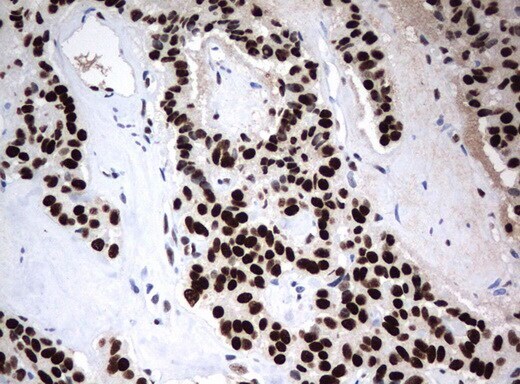

- Immunohistochemical staining of paraffin-embedded human Kidney tissue using anti-ZSCAN18 mouse monoclonal antibody. (UM500081; heat-induced epitope retrieval by 10mM citric buffer, pH6.0, 120°C for 3min)